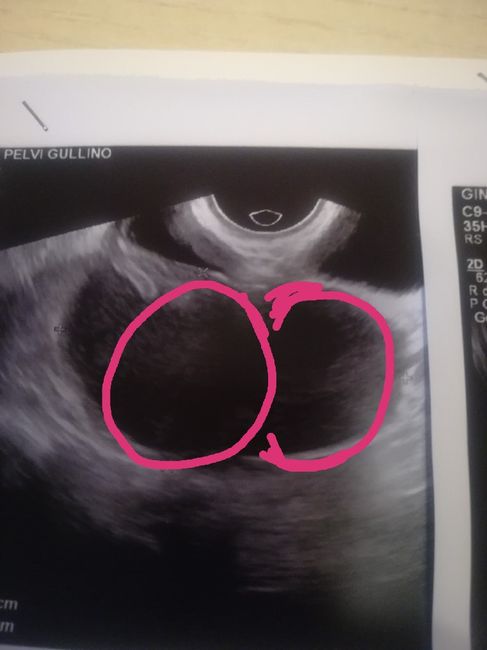

Per farti capire meglio. Le cisti sono quelle cerchiate.

Non sò se potete aiuarmi... 1

Non lo so ma non sono quelle le cisti. Le cisti sono quelle macchie scure in centro.

Comunque cara questa è la mia eco. Sono due e non una.

Non sò se potete aiuarmi... 3